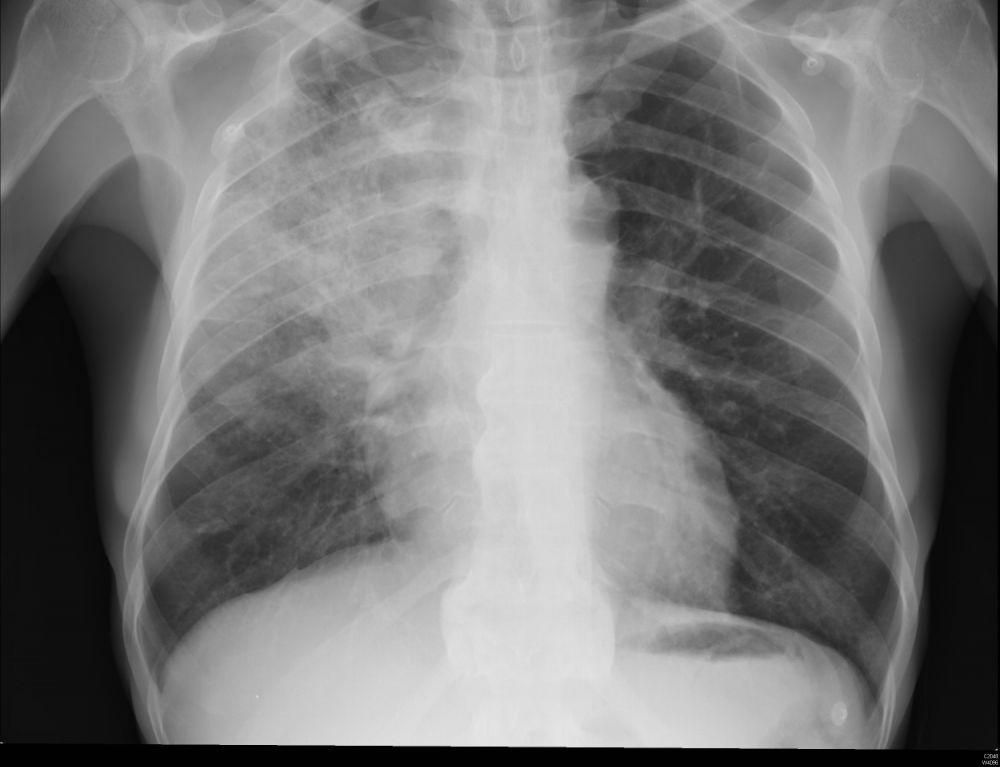

Pneumonia adalah infeksi yang menyerang kantung udara kecil di paru-paru (alveoli). Kantung-kantung ini dapat terisi nanah atau cairan, dan penyakit ini bisa berkembang menjadi ringan atau berat tergantung pada faktor-faktor seperti usia dan jenis pneumonia yang dialami. Mengetahui jenis pneumonia sangat penting agar bisa mendapatkan perawatan yang tepat. Berikut adalah beberapa jenis pneumonia yang umum ditemukan: